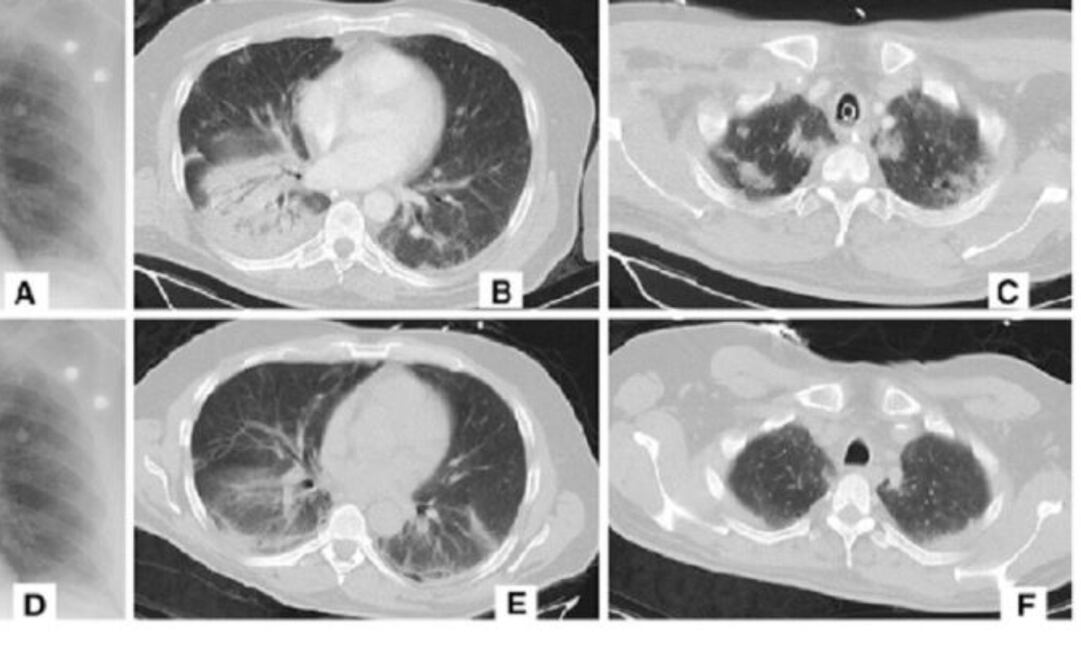

De acuerdo con un informe de Nikkei’s Asian Review, Alibaba afirmó que su nuevo sistema puede detectar coronavirus en tomografías computarizadas de pacientes con una precisión del 96% contra los casos de neumonía viral.

Solo toma 20 segundos para que la IA tome una determinación; según el informe, los humanos generalmente tardan unos 15 minutos en diagnosticar la enfermedad, ya que puede haber más de 300 imágenes para evaluar.

De acuerdo con The Next Web, el sistema fue entrenado en imágenes y datos de 5 mil casos confirmados de coronavirus y ya ha sido probado en hospitales de toda China. Según el informe, al menos 100 centros de salud emplean actualmente la IA de Alibaba.